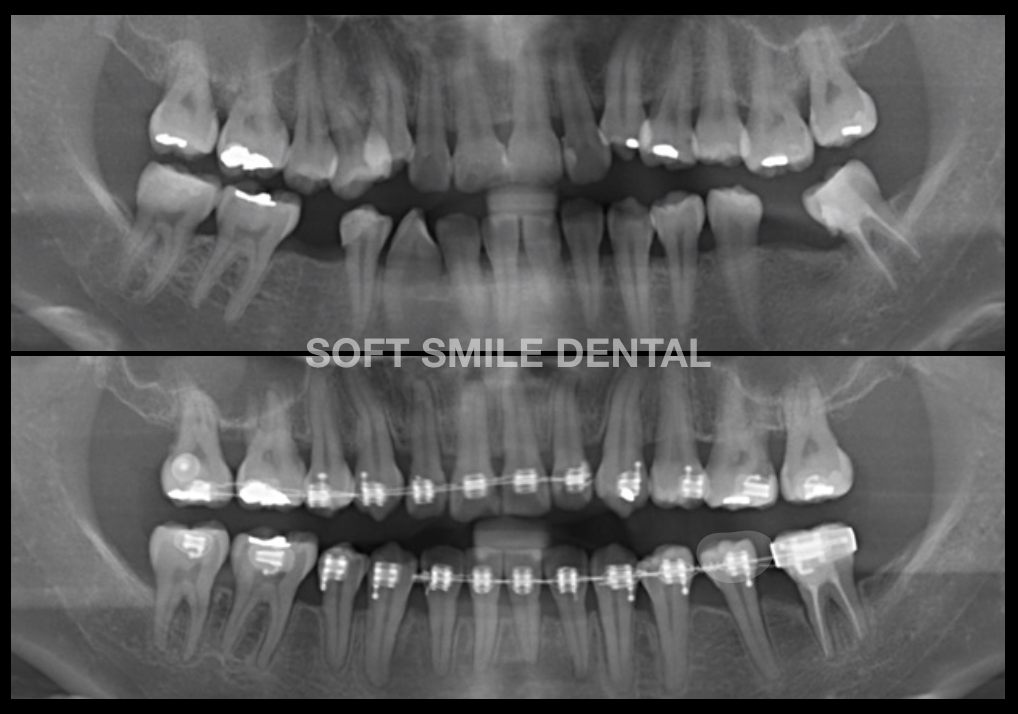

• GHÉP XƯƠNG HỖ TRỢ CHỈNH NHA

Là kỹ thuật ghép xương hồi phục xương nâng đỡ răng, hỗ trợ không gian để răng di chuyển dưới lực chỉnh nha, hoặc điều trị các ca chỉnh nha gây tiêu xương. Ngoài ra, ghép xương cho phép răng di chuyển vào các vị trí thiếu xương ở những ca mất răng lâu ngày.